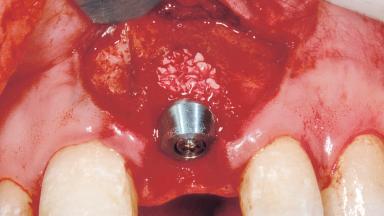

Immediate Placement of an Implant in a Maxillary Left Central Incisor Site

A 33-year-old female patient presented with an upper left central incisor that required extraction after a failed endodontic therapy. The tooth had been traumatized when the patient was a teenager and had undergone several endodontic treatments, including two apicectomy procedures. The patient was in good health and did not smoke. Clinical examination showed that the patient had a high lip line. In full smile, the gingival margins of the upper teeth were visible to the first molars. The gingival margins of central incisors 11 and 21 were only just showing. Examination of tooth 21 confirmed that the tooth was mobile and had hypererupted by 1 mm.

Bone Augmentation Horizontal|Simultaneous

Augmentation Materials Xenogenous|Membrane

Placement Protocol Immediate implant placement

Socket Morphology Single-root socket

Socket Integrity Damage to one or more bone walls

Bone Volume Damage to one or more socket walls